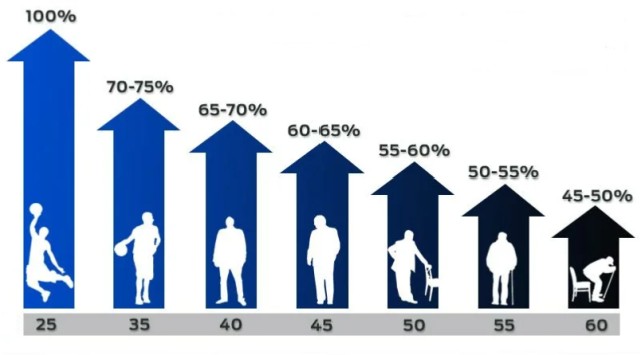

– Oczywiście, nawet u starszych mężczyzn. Istnieje wiele błędnych przekonań na ten temat. Niestety, wiele osób uważa, że utrata aktywności seksualnej po 50. lub 60. roku życia jest czymś naturalnym i nic nie można na to poradzić. To nieprawda. Naturalny spadek potencji dotyczy głównie mężczyzn powyżej 80 roku życia. Jeśli dzieje się to wcześniej, współczesne osiągnięcia farmakologii sprawiają, że jej przywrócenie jest znacznie łatwiejsze, niż się wydaje. Nie jest to proces nieunikniony – jest to problem, dla którego istnieje rozwiązanie!